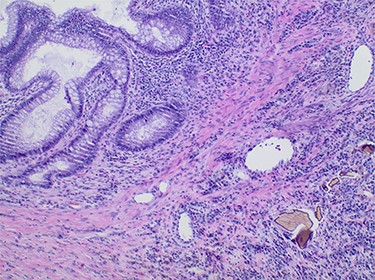

A 65-year-old African American female with history of end-stage renal disease secondary to autosomal dominant polycystic kidney disease presented our Emergency Department with abdominal pain and hematochezia. She was evaluated with esophagogastroduodenoscopy and colonoscopy, which showed multiple non-bleeding sigmoid diverticula and descending colon mucosal erosions consistent with colitis. She was treated medically with metronidazole and ciprofloxacin. Her symptoms recurred 1-week after hospital discharge. She complained of intermittent, severe left lower quadrant pain with associated nausea and non-bilious emesis. Computed tomography (CT) on re-admission showed thickening of the descending-sigmoid colon junction with fluid-filled, dilated colon proximally (Fig. 1). Given symptoms and CT imaging consistent with early large bowel obstruction, the patient was taken to the operating room for exploratory laparotomy, sigmoid colectomy and end colostomy. Surgical pathology revealed pericolonic abscess and Sevelamer crystals (Fig. 2). The patient’s Sevelamer was discontinued, and her postoperative course was uncomplicated. She was seen back for planned elective colostomy reversal 4 months after her initial operation.

Computed tomography of the abdomen and pelvis showing focal narrowing of the sigmoid colon with proximal colonic dilatation.